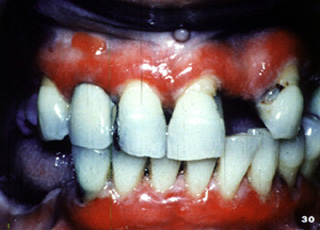

El penfigoide benigno tiene una marcada tendencia a involucrar la encía marginal. La descripción clínica a menudo usada para estas lesiones es "gingivitis descamativa" Debe señalarse que ésta es sólo una descripción clínica y no un diagnóstico definitivo. En la encía  tiene una marcada apariencia eritematosa.

Aquí hay otro paciente con la encía afectada por la enfermedada..

Aquí hay  áreas de ulceración y descamación gingival.